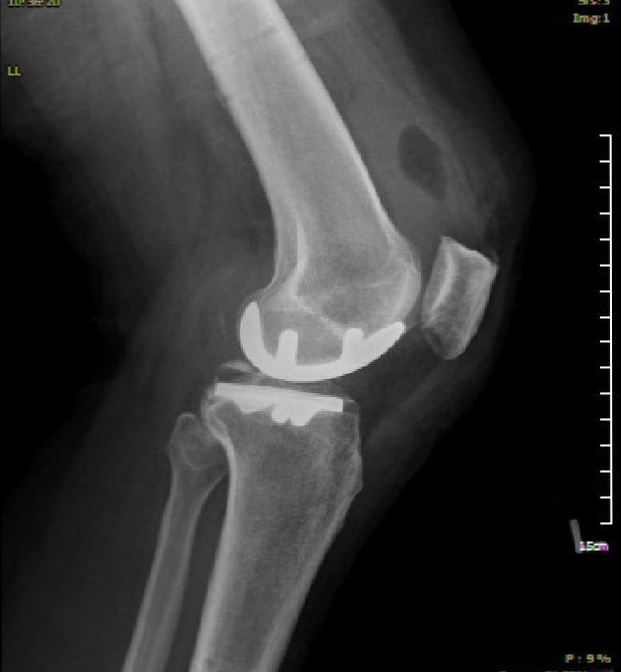

These are the x-rays with the implants in: